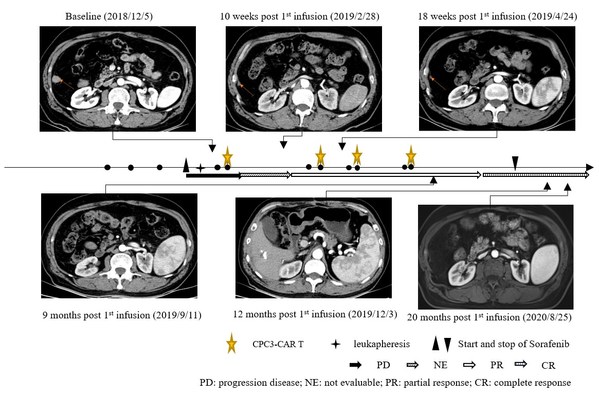

案例显示,一名患有乙型肝炎病毒(HBV)相关肝细胞癌的60岁亚裔男性,2018年5月接受手术,2018年8月术后肝癌复发并出现肺转移,随后接受经动脉化疗栓塞治疗(TACE)处理肝部病灶和介入消融处理肺部转移,但于2018年11月6日出现疾病进展,进而入组本临床试验。入组后,患者接受了单采,用于GPC3 CAR-T细胞的制备。单采后7天,患者开始服用索拉非尼,每天两次,每次400毫克。患者接受了4个周期的GPC3 CAR-T细胞(CT011)治疗,每个周期分为两次输注。在接受CT011治疗的每个周期之前,进行清淋化疗预处理。共输注4×109 个GPC3 CAR-T细胞。

CT011联合索拉非尼治疗耐受性良好。患者从第3个月开始达到部分缓解(PR),并在第一个 CT011 输注周期后的第12个月达到完全缓解。肿瘤超过36个月没有进展,在第一次输注后保持完全缓解状态超过24个月。